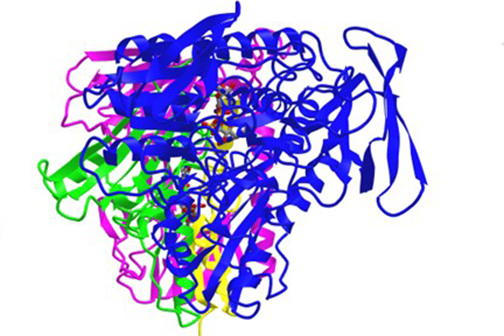

Scientists at LSU Health New Orleans’ Neuroscience Center of Excellence, led by Nicolas Bazan, MD, PhD, Boyd Professor and Director, have identified a new mechanism that regulates a protein key for cell survival. It appears to protect against the excessive oxidative stress that precedes the development of neurodegenerative diseases of the brain and eye. More